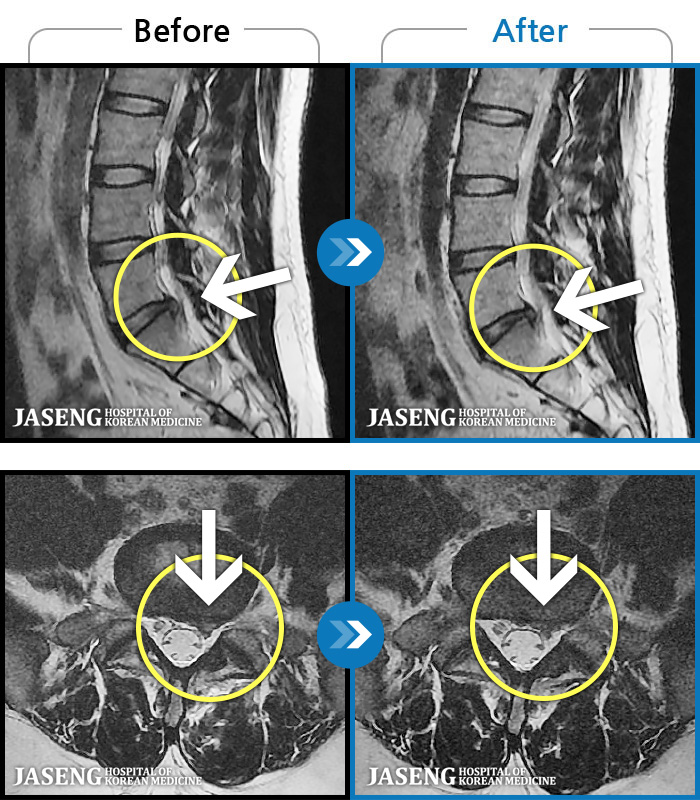

허리통증으로 일상이 멈췄다.

2023.03.13 ~ 2024.05.08